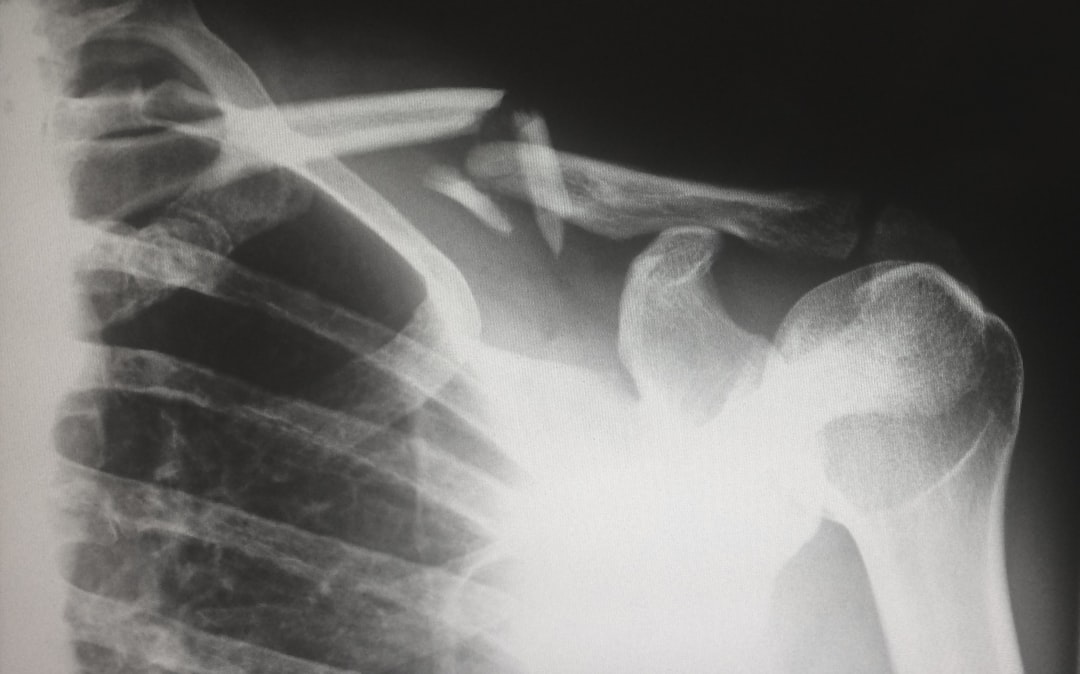

이어지는 과정에서는 X-ray와 CT 스캔을 통해 정확한 상태를 확인합니다. 이러한 검사는 골반의 상태를 면밀히 분석하여, 골절의 종류와 심각성을 판단하는 데 큰 역할을 합니다. 이 모든 과정에서 청주시 골반 골절 진단 및 수술 전문 병원의 전문성이 돋보입니다. 초기 진단에 따라 치료 방향이 정해지니, 이 점은 특히 주의해야 할 사항입니다. 다음 단계로 넘어가 보세요.